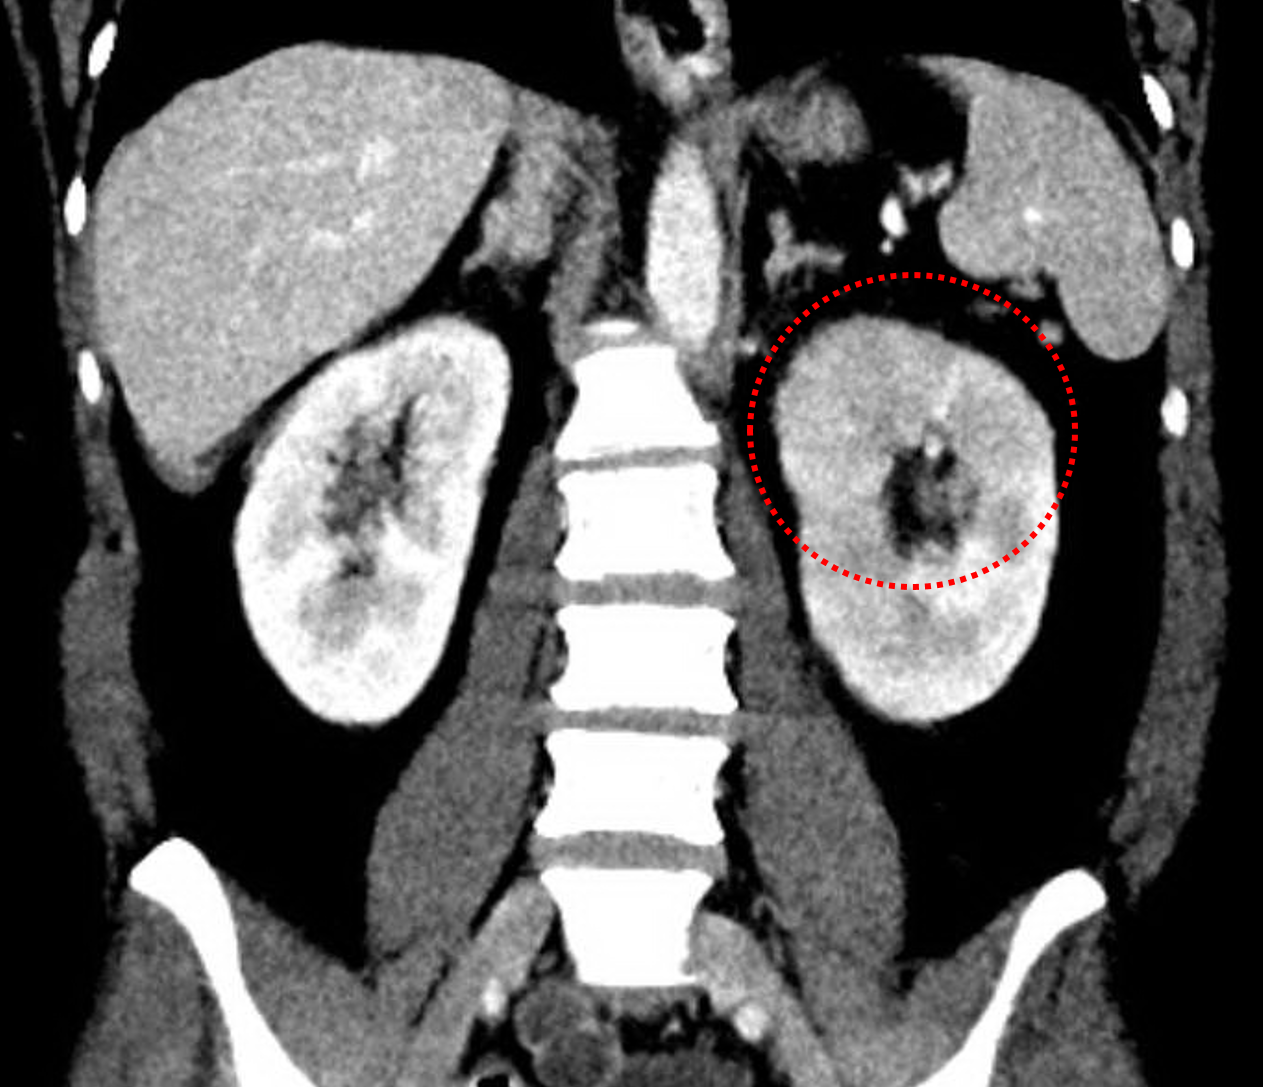

Age: 44

Sex: Female

Indication: Abdominal pain, fever

Sample ReportFindings concerning for left pyelonephritis. No hydronephrosis or evidence of renal/perinephric abscess.